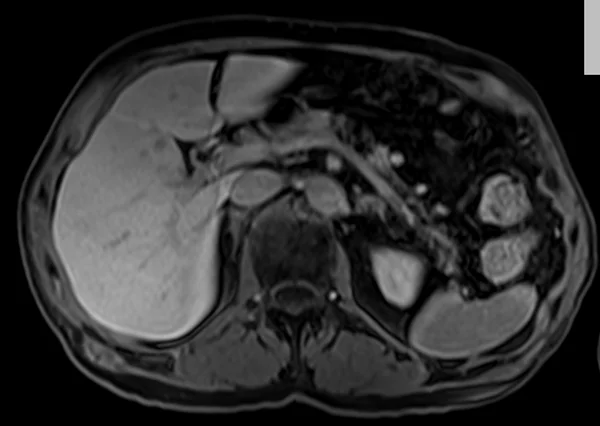

delay 5min 3 - MRI